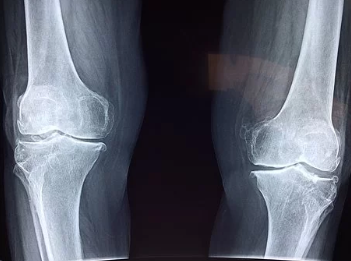

그리고 만약 고관절 통증을 겪고 있다면 빠른 기간 내에 병원을 찾아 물리치료, 주사치료, 약물치료, 운동 치료 등을 통해 증상을 개선해야 합니다. 고관절 통증이 지속되면 무릎 통증으로 내려오는 등 관절 퇴행을 앞당기게 되므로 꼭 빠른 치료에 관심을 가지시길 바랍니다.